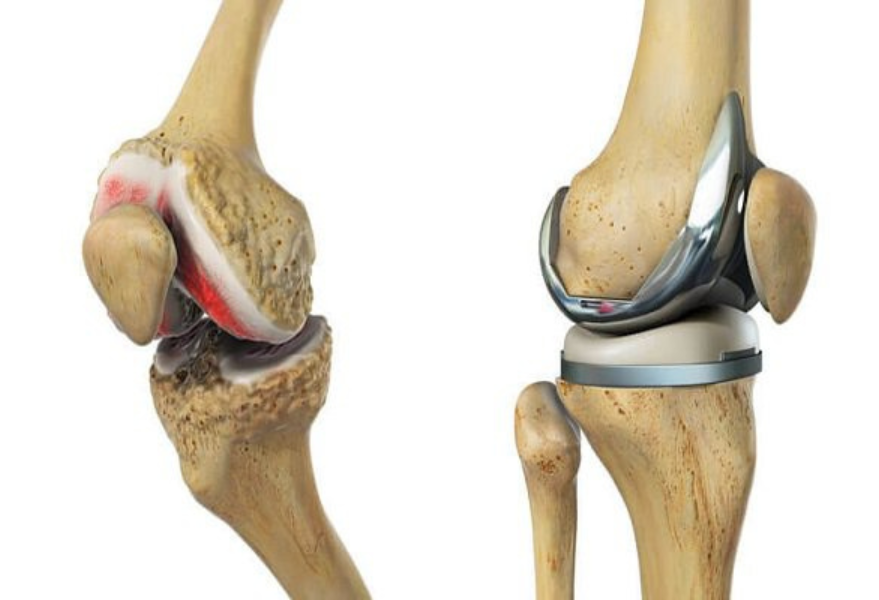

Phẫu thuật thay khớp gối (knee replacement) là phương pháp thay thế các bề mặt khớp gối đã hư hỏng bằng khớp nhân tạo nhằm giảm đau, phục hồi khả năng vận động và nâng cao chất lượng cuộc sống cho người bệnh.

Hình ảnh minh họa thay khớp gối giúp phục hồi vận động và giảm đau do thoái hóa.

Một khớp gối nhân tạo thường có cấu tạo mô phỏng khớp tự nhiên với ba thành phần chính:

Phần đùi:Gắn vào đầu dưới xương đùi, thường làm từ hợp kim bền (ví dụ cobalt–chromium) tạo bề mặt trơn nhẵn giúp khớp vận động mượt.

Phần chày:Gắn vào đầu trên xương chày, gồm đế kim loại chịu lực và miếng đệm polyethylene hấp thụ va chạm, giảm ma sát khi cử động.

Phần xương bánh chè:Là miếng đệm bằng polyethylene gắn vào mặt sau xương bánh chè, hỗ trợ trượt êm khi gập – duỗi gối.

Các vật liệu này có tính tương thích sinh học cao, ít gây phản ứng và có thể sử dụng bền vững trong nhiều năm khi người bệnh tuân thủ chăm sóc, luyện tập đúng hướng dẫn.